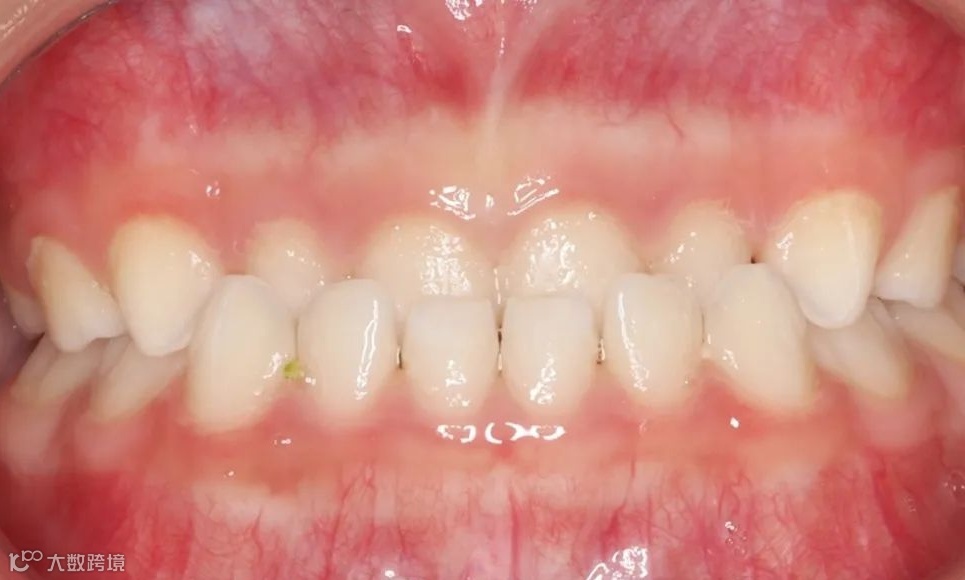

治疗前右侧咬𬌗相

治疗前正面向咬𬌗相

治疗前左侧咬𬌗相

患儿戴用Twin-Block矫治器,在引导下颌向前的同时扩宽上颌牙弓,内收上前牙。

治疗后右侧咬𬌗相

治疗后正面咬𬌗相

治疗后左侧咬𬌗相